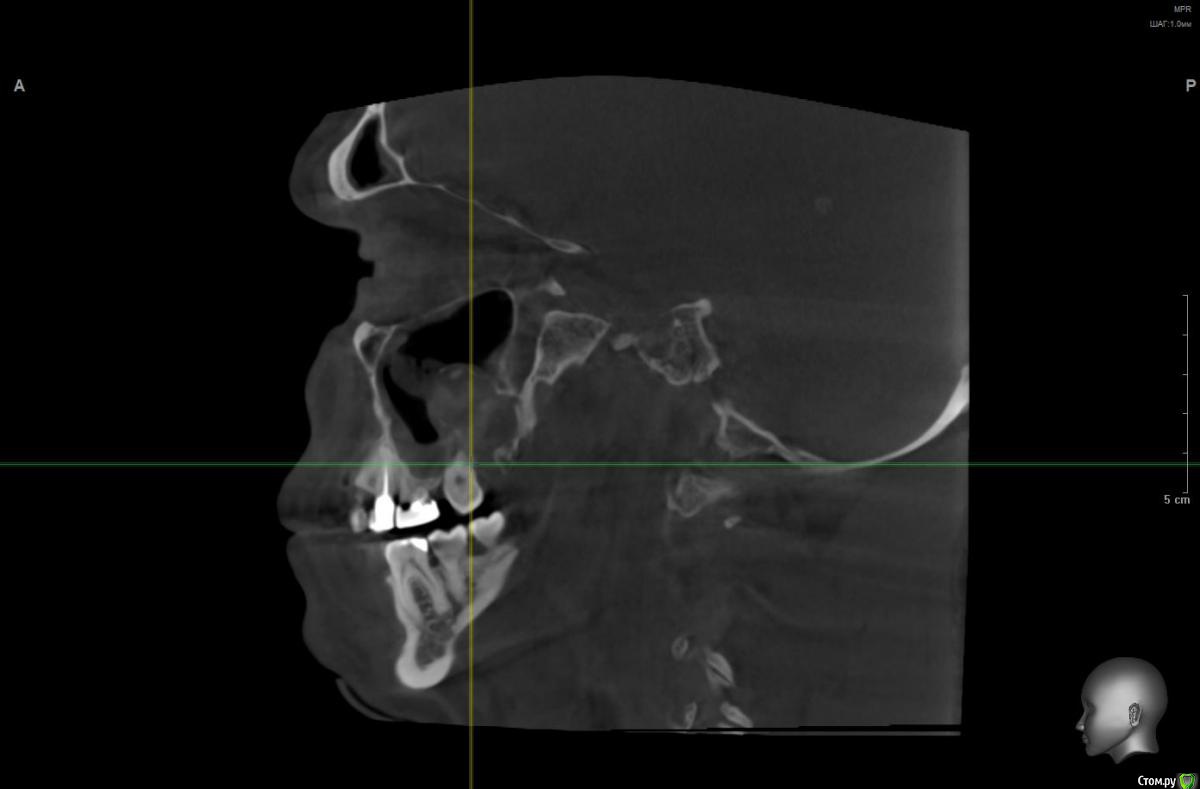

wladdX Опубликовано 5 марта, 2019 Поделиться Опубликовано 5 марта, 2019 Корональная проекция Сагиттальная справа Сагиттальная слева 16 26 28 Ссылка на комментарий

kramer Опубликовано 5 марта, 2019 Поделиться Опубликовано 5 марта, 2019 В общем скачал я КТ. Что касается зуба 26, да, там есть признаки воспаления вокруг корней, лечить / удалять зависит от состояния тканей зуба и возможностей врача. Но лично мне не кажется, что этот зуб играет главную роль в возникшем гайморите. Обратите внимание, в области 8 зуба (см. срез) внутри пазухи есть некий очаг, содержащий неоднородные по плотности элементы (более светлые включения, а выше пузырьки воздуха). Снимок не особо четкий, но такое ощущение, что в области 8 зуба вообще нарушена целостность боковой стенки пазухи. Кроме того, с правой стороны все зубы в порядке, а явления гайморита тоже имеются (там вообще почти вся пазуха забита). Соустья с носом закрыты. В общем, в данной ситуации я бы более детально обследовал 8 зуб, если там все нормально, то пусть ЛОРы эндоскопически лезут в пазухи и убирают это все. Ссылка на комментарий